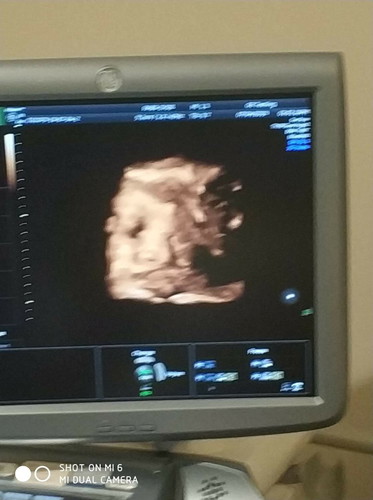

40w.6d.

40wแล้ว แต่หนูยังไม่ออกมาเลยจ้าไม่ปวดท้องปากมดลูกไม่เปิดสักที หมอบอกออกมาคงเดินได้เลย อยากเจอแล้ว ปล.อิพ่อถ่าย มือสั่นตื่นเต้นอยากเจอลูก5555